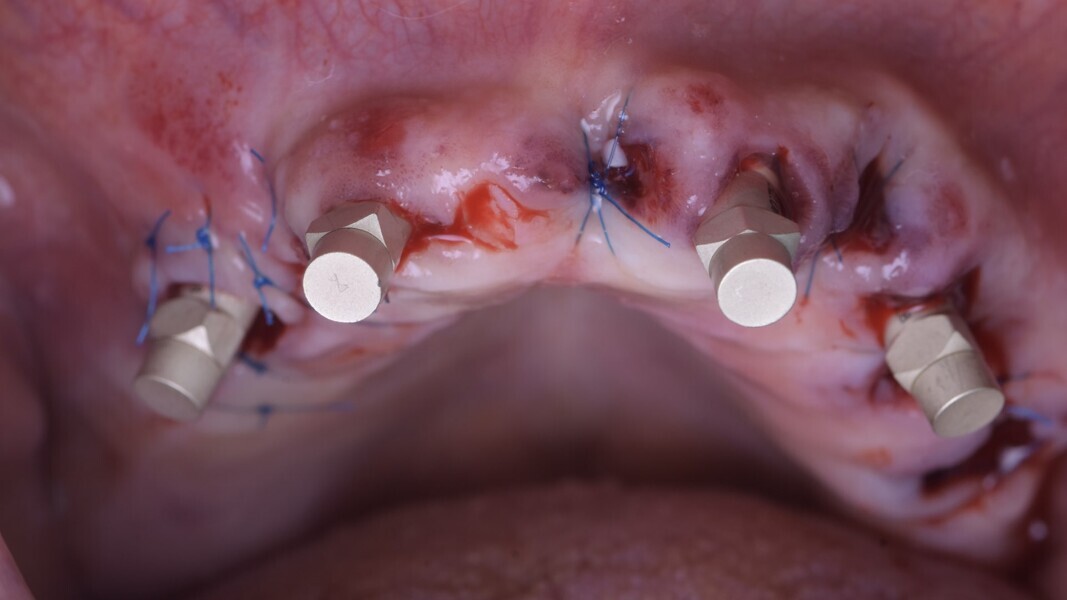

Les deux implants antérieurs seront tout d’abord posés afin de respecter un positionnement idéal pour un futur vissage palatin de la prothèse, puis les deux implants postérieurs seront inclinés à 20 degrés (protocole classique décrit par le Dr Malo).4 Ensuite des piliers coniques multi-unit droits en antérieur et de 17 degrés en postérieurs, sont vissés sur nos implants. Enfin les scan bodies sont placés avant les sutures, afin d’assurer un contrôle visuel de leur bonne position, ainsi qu’une bonne adaptation.